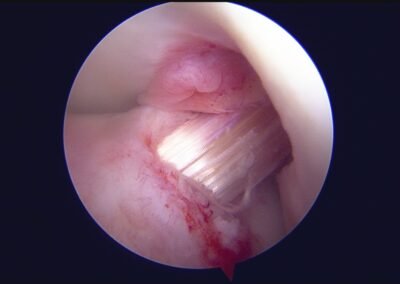

GalleryShoulder rotator cuff repair Meniscus root repair Meniscus repair Bankart repair for recurrent shoulder dislocation ACL reconstruction Machines Instruments